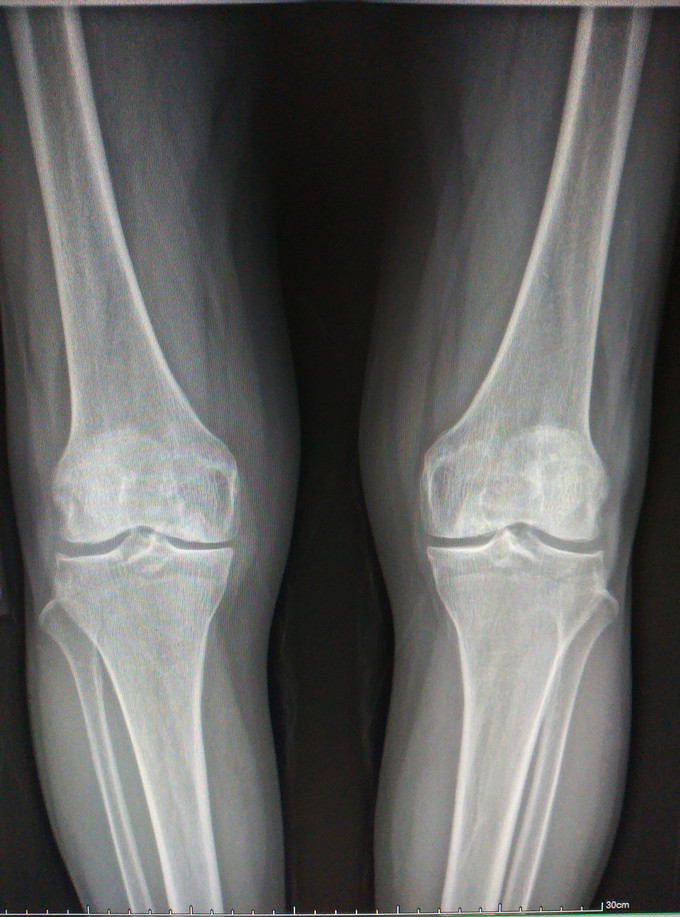

右膝关节疼痛5年 患者约5年前无明显诱因逐渐出现右膝关节疼痛,为持续性胀痛; 疼痛在步行活动时疼痛明显加剧,持续性胀痛。疼痛在长时间步行后加重。休息可有部分缓解。患者无发热,无其他关节疼痛。无下肢麻木乏力等。患者在当地服用中药,玻璃酸钠等保守治疗,无明显效果

双下肢等长,力线可。双侧膝关节屈伸活动好。无内外侧松弛。侧方应力试验阴性。前后抽屉试验阴性。 X片提示膝关节退变。

膝关节骨性关节炎,内侧间室退行性病变。 膝关节单髁置换术。